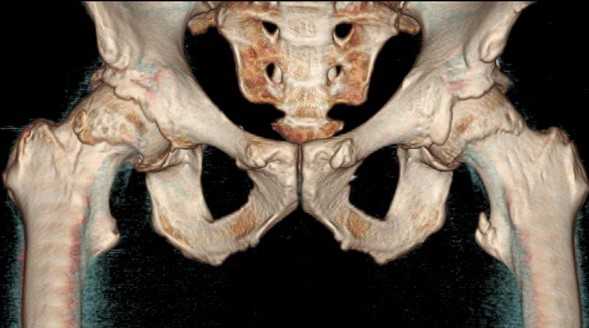

КТ тазобедренного сустава

Боли в области сочленения возникают при патологических изменениях пара- (расположенных рядом) и интраартикулярных структур. К внутренним факторам относят:

поражение вертлужной впадины и бедренной кости;

пролиферативные нарушения синовиальной оболочки;

дегенеративные поражения хряща и пр.

Трехмерная реконструкция тазобедренных сочленений

Внесуставные причины появления болей:

поражение крестцово-подвздошного и лонного сочленений;

КТ тазобедренного сустава используют для дифференциальной диагностики заболеваний, установления причины и характера патологического процесса.